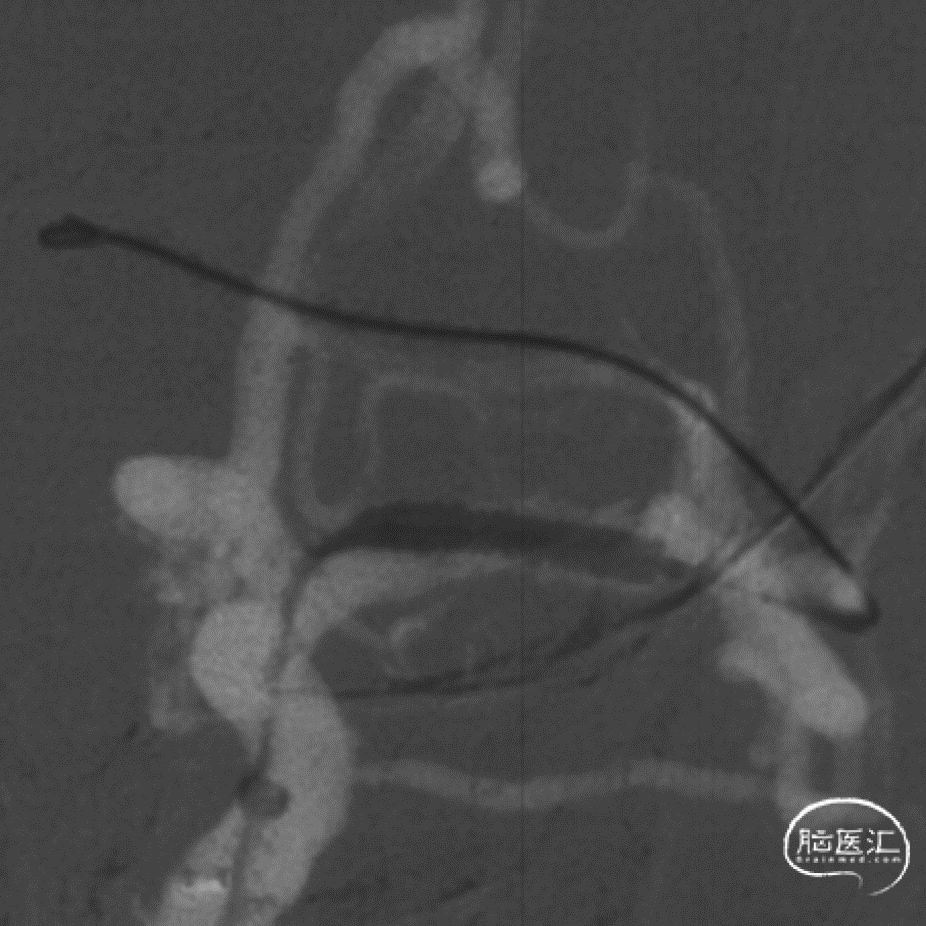

导丝导引Fastunnel® 2/15 输送型球囊扩张导管到位。

手推造影确认球囊位置,完全覆盖狭窄。

Fastunnel® 2/15 输送型球囊扩张导管缓慢扩张至10atm,对应球囊直径2.13mm。

回撤球囊后,导丝从Fastunnel®输送型球囊扩张导管撤出,备支架释放。

将支架定位于狭窄远端、分叉以近正常段,完整覆盖病变。